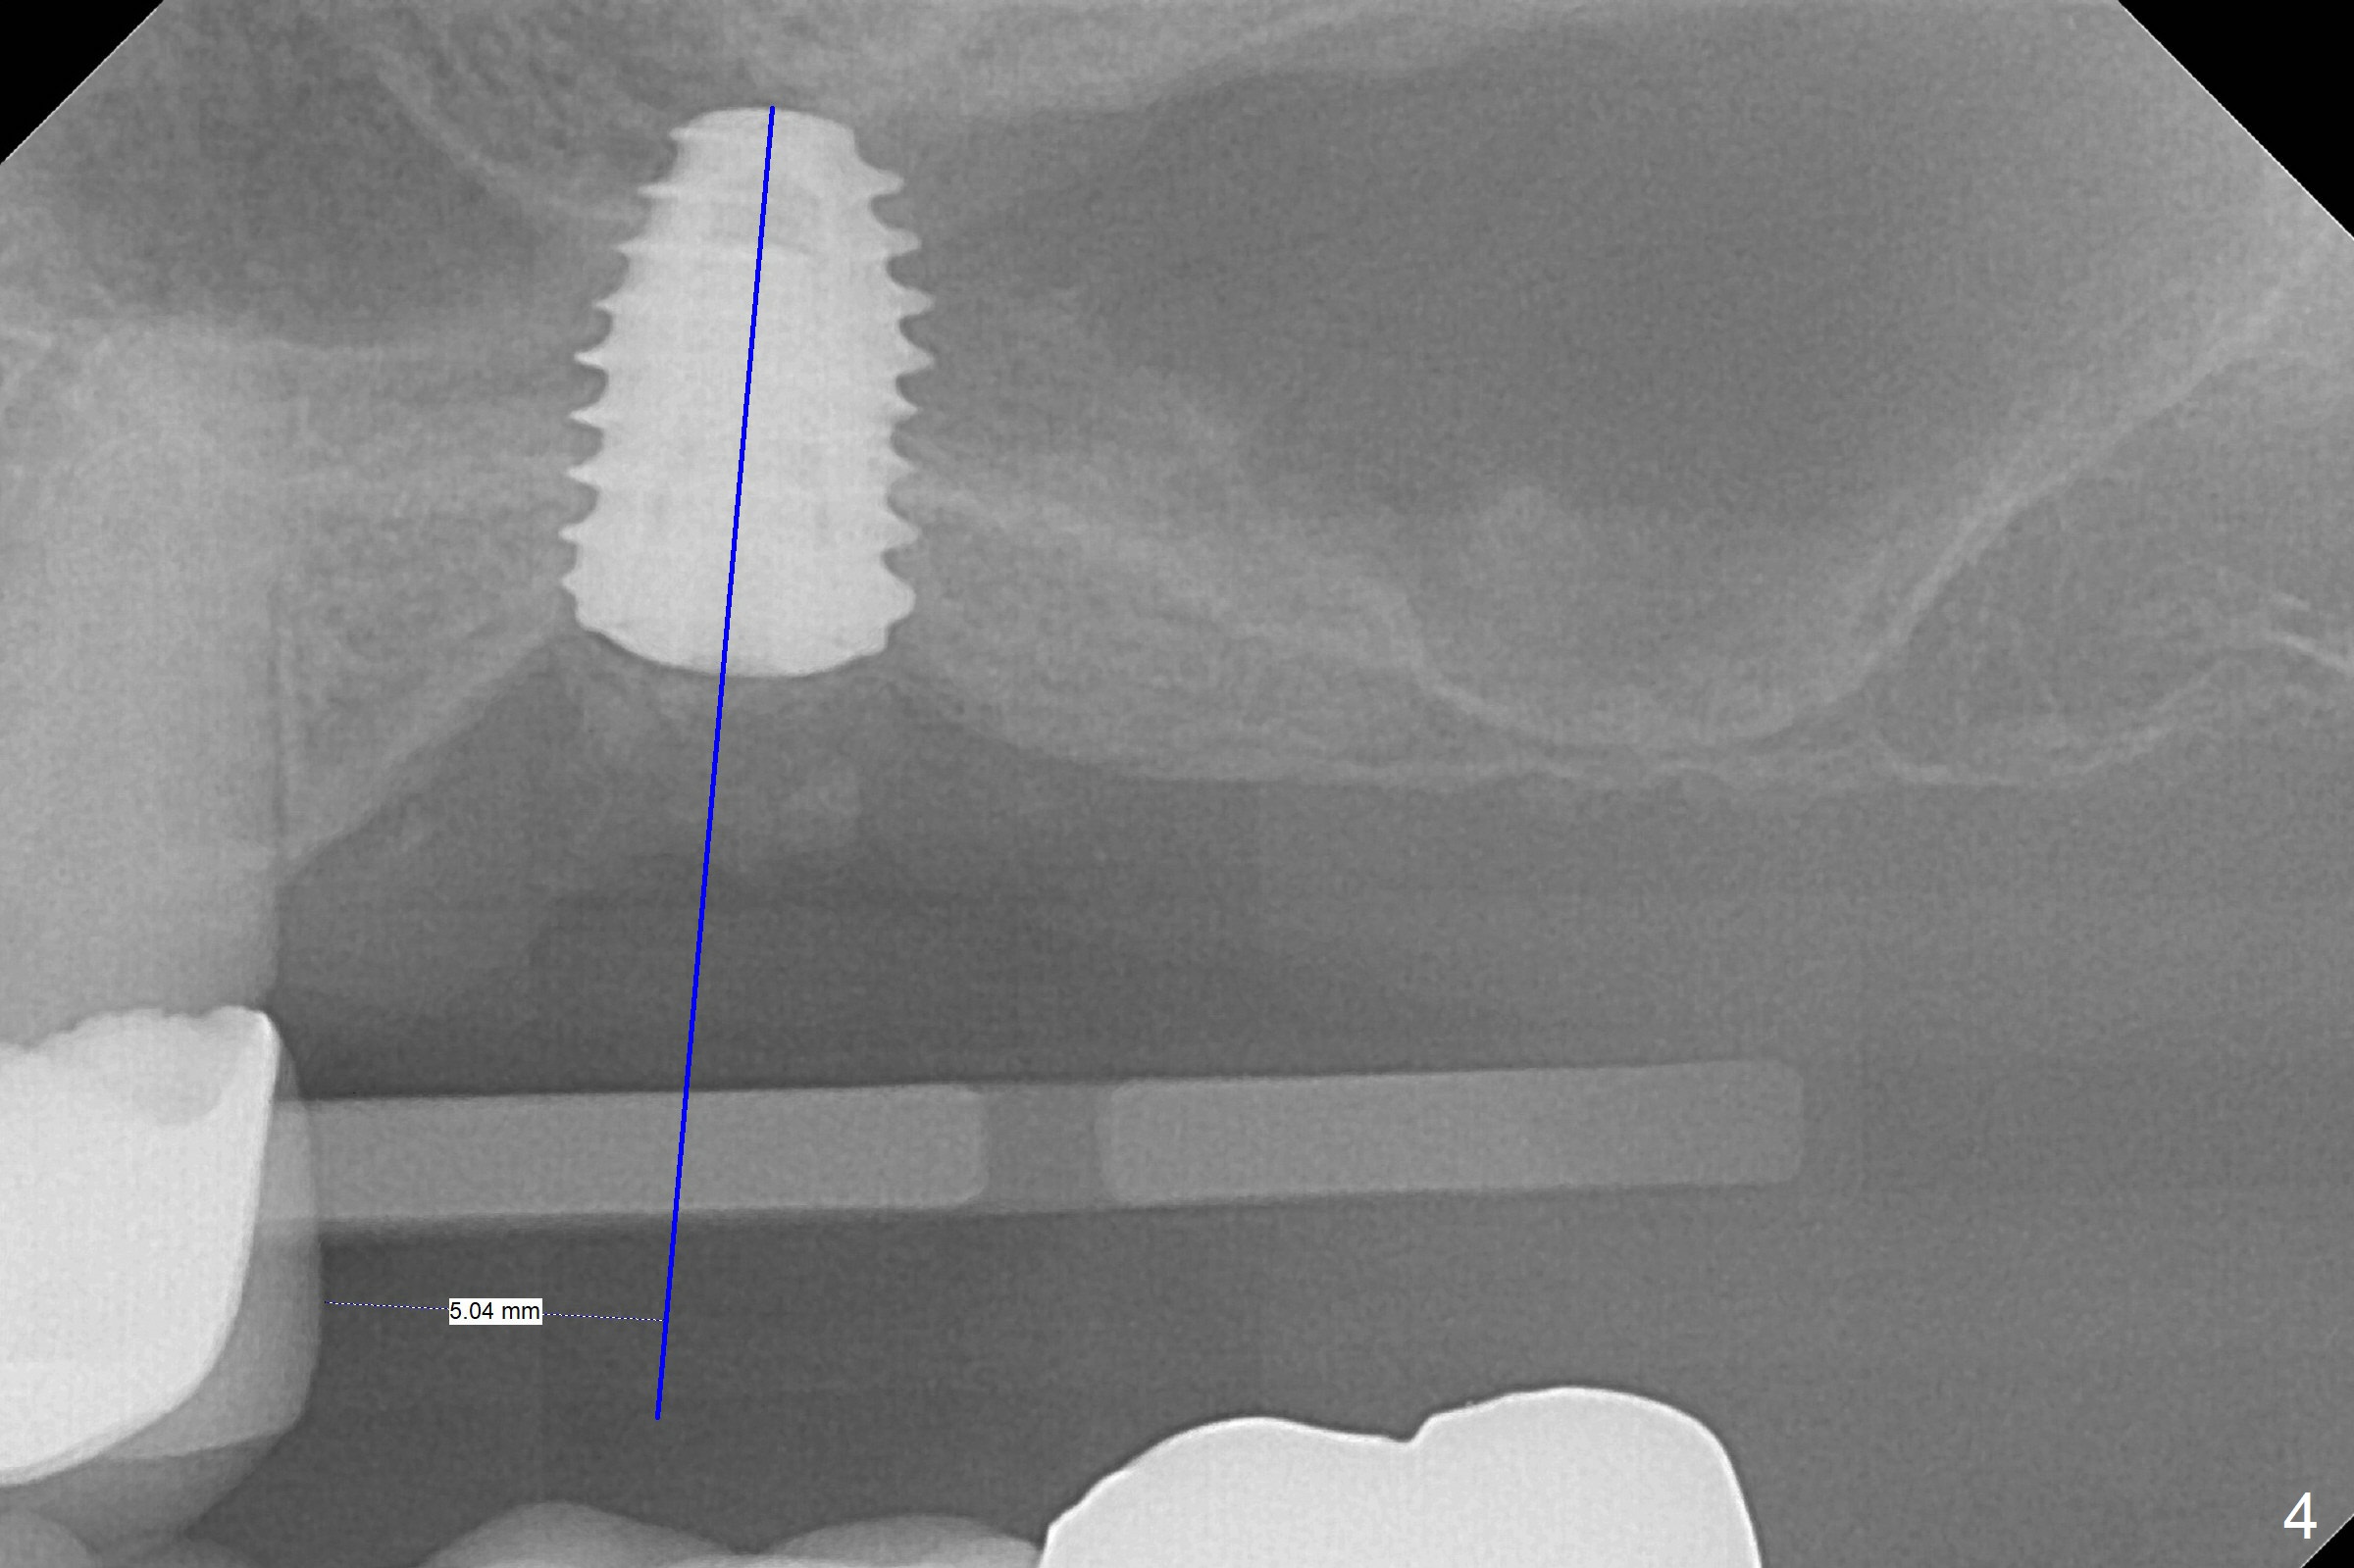

When the non-osteointegrated implant is removed, the sinus membrane is found to have been perforated. There is a history of clear discharge immediately postop ~ 1 year ago. Against the common wisdom, a 5x10 mm dummy implant is inserted with intention to correct the trajectory and 50 Ncm (Fig.1). With placement of Osteogen plug (presumably for repair of the perforation) and limited amount of Vanilla at the osteotomy, a 5x7.3 mm IS implant with SLA surface treatment is placed (Fig.2, ~ 40 Ncm). When the implant is further seated (Fig.3 arrow with bone graft coronally *)), its trajectory is within the normal limit (Fig.4 blue line). If the implant fails again, it must be due to the mild sinus infection. Bone graft, or preferably Osteogen Plug (collagen with osteoconductive ability) should have been done first. Mild tenderness exists with use of Water Pik 7 months post 2nd placement (Fig.5). Uncover shows that the implant is stable. A 6x3 mm healing abutment is placed. Next appointment a temporary crown will be fabricated for progressive loading. The abutment screw needs retightening 8 months post cementation, probably related to poor crown/implant ratio and missing 2nd molar (Fig.6).